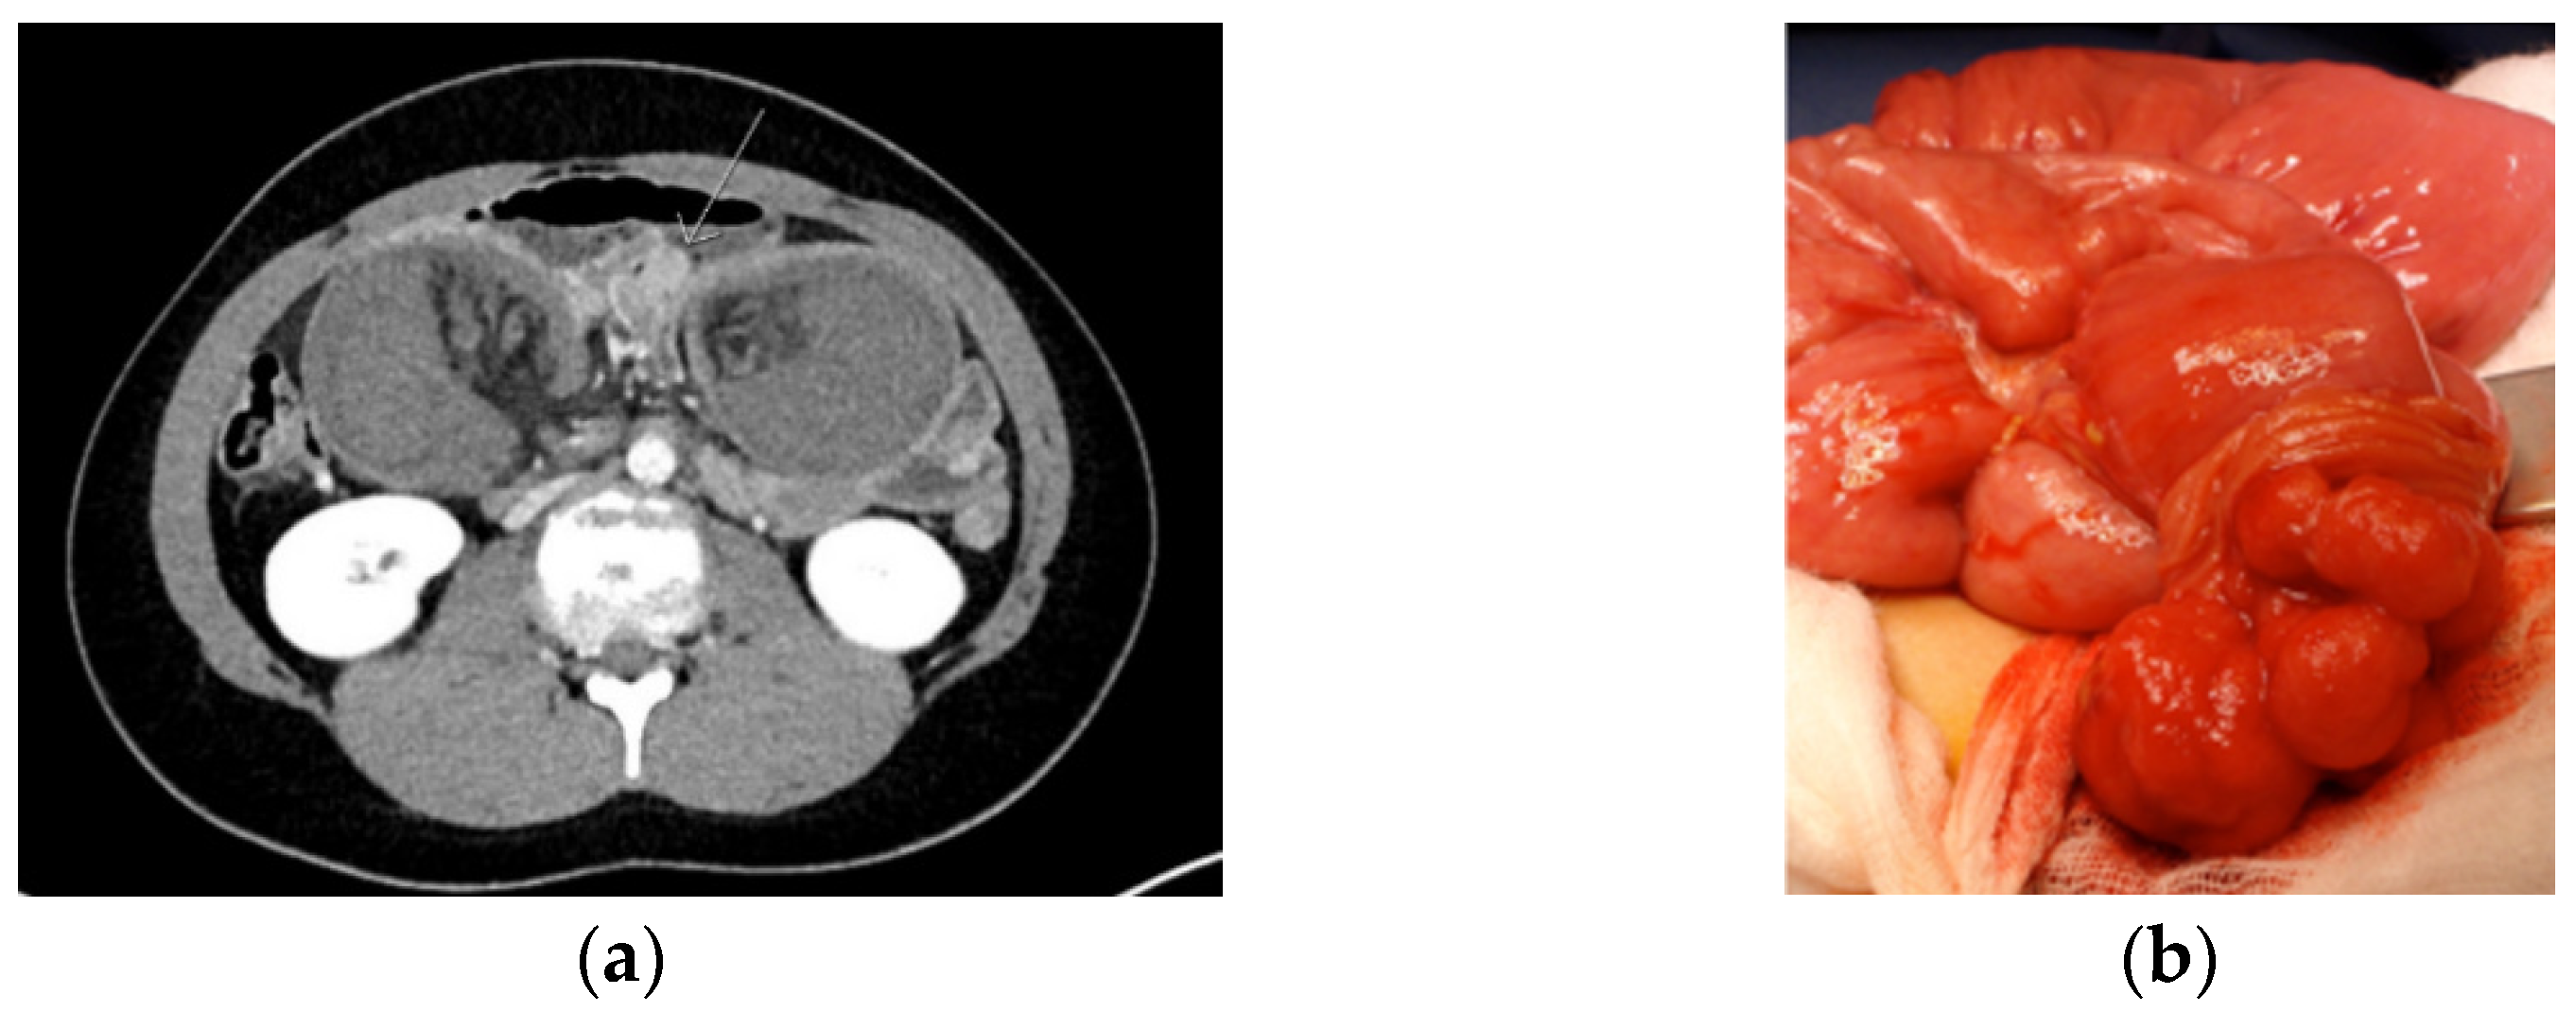

Intussusception occurs when a proximal segment of bowel and its mesentery slides into the lumen of the adjacent distal segment. In PJS, a polyp typically forms the hypomochlion that subsequently leads to intussusception due to bowel peristalsis. Intussusception is a surgical emergency leading to bowel ischemia, necrosis, and perforation when untreated (Figure 2).

Figure 2.

CT image of intussusception (a) and to be resected polyp (b) in a Peutz–Jeghers syndrome patient.

In PJS, the risk of intussusception is estimated to be 44% by the age of 10 and about 50% by the age of 20% [52]. The risk of intussusception increases with increasing polyp size of 15 mm and larger [48]. The surgical reduction of intussusception should be undertaken without delay to avoid necrosis and resection of the small bowel. Usually, laparotomy is the safest option, but in selected, milder cases, laparoscopy can be considered. When ischemia is reversible, resection of the bowel should not be done but only a polypectomy. In addition, intraoperative enteroscopy through enterotomy is recommended to find and remove over 15 mm size polyps. If enteroscopy is not available, illumination and thorough palpation of the small bowel is recommended in order to palpate and remove larger polyps [53]. Up to 40% of PJS patients requiring laparotomy before the age of 18 will require a new laparotomy within 5 years of the first laparotomy [48]. The risk of malignant polyp during childhood is zero and low also during adulthood being 2.3–4.5% according to the literature [12,19,52,54].